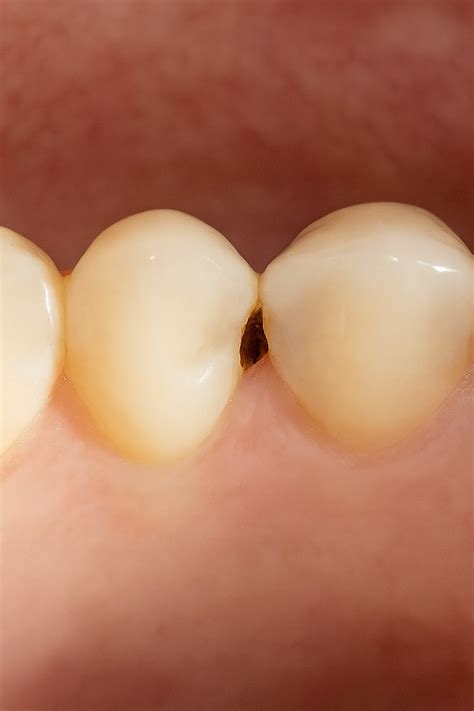

Las caries dentales son lesiones en el diente causadas por ácidos que generan las bacterias de la boca al descomponer los azúcares de los alimentos. Aunque algunas caries pueden ser claramente visibles -con aspecto de manchas oscuras o cavidades en los dientes-, muchas otras no son tan evidentes en sus primeras etapas.

- Caries en la corona: Son más fáciles de detectar visualmente, pero las radiografías ayudan a determinar su extensión.